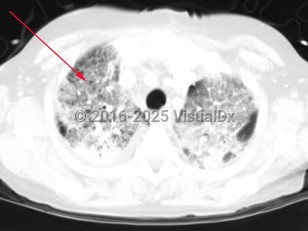

Haemophilus influenzae pneumonia

Symptoms include fever, cough, and shortness of breath. Symptoms may differ depending on the type of pneumonia (either segmental or bronchopneumonia). Patients with a segmental pneumonia can present with abrupt onset of fever, pleuritic chest pain, and sore throat. These patients tend to develop bacteremia more frequently than those with bronchopneumonia. Patients with bronchopneumonia can present with constitutional symptoms, tachypnea, and a mild fever. Haemophilus influenzae more commonly presents as a bronchopneumonia.